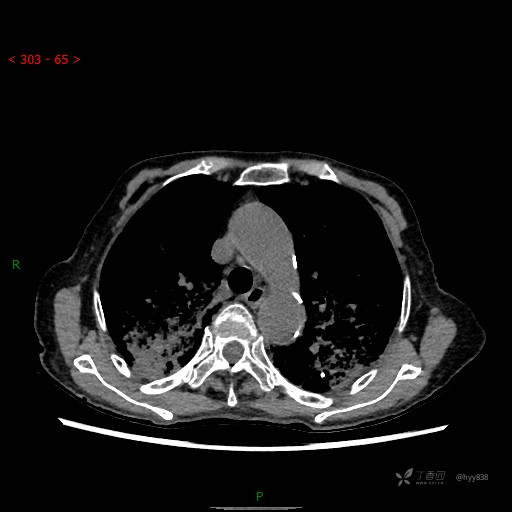

肺部弥漫性、疑难病变,感染或肿瘤?一元论或二元论?贴贴精彩---结果公布~

简要病史:患者10余天劳累后出现发热,最高体温达39.5℃,无畏寒、寒战、鼻塞、流涕,无头晕、头痛,无心慌、胸闷、胸痛,无咳嗽、咳痰、气喘,无反酸、烧心、恶心呕吐,无腹痛、腹胀等不适,于2022-5-31至当地中医医院住院治疗,诊断为重症肺炎,予以抗感染、抗病毒等对症支持治疗,仍反复发热,现为求进一步诊治,至我院门诊就诊,门诊以“重症肺炎”收入我科。 起病以来,患者精神、饮食、睡眠差,大小便正常,体力下降,体重无明显变化。

临床诊断:重症肺炎

胸部CT平扫